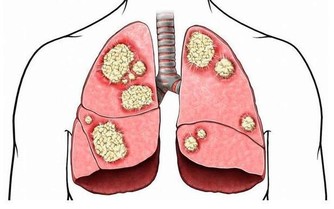

3. 便便變細,排不盡

若是平時排的便便較粗,突然間變成了鉛筆一般的柔軟細便,並且總有排不盡的感覺,就要特別注意有可能是大腸癌導致的,需要高度警惕,必要時到正規醫院消化內科就診。